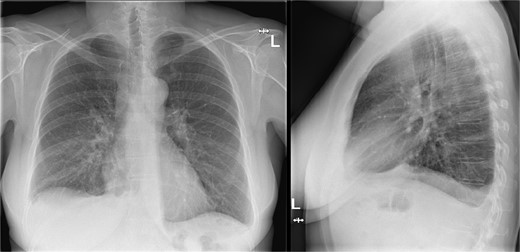

Additional imaging diagnostics with X-ray demonstrated bilateral pleural effusion, more apparent at the right side (Fig. 1). A subsequent computed tomography (CT) scan showed no signs of pulmonary embolism and confirmed the pleural effusion (Fig. 2). In addition, air was seen in the anterior mediastinum (pneumomediastinum). Both air and pleural effusion were attributed to normal healing after the recent VAMLA, and in the absence of clinical alarm symptoms the patient was sent home. In the absence of loculation or contrast captation, the bilateral pleural effusion had no radiological signs of empyema. One of the symptoms of pleural effusion is dyspnea which was also present in the patient. In addition, there was no suspicion of an infectious cause with normal vital values with a temperature of 37.7°C and no significant elevation of WBC or CRP. It was suspected that the effusion was postoperative or reactive to the suspected lung cancer. Regarding the hoarseness, the most likely cause was post-operative swelling of the surgical area. As the hoarseness did not occur immediately post-operative, iatrogenic recurrent nerve injury was not suspected.

CT-scan during visit to the emergency department confirming the pleural effusion attributed as reactive or postoperative.